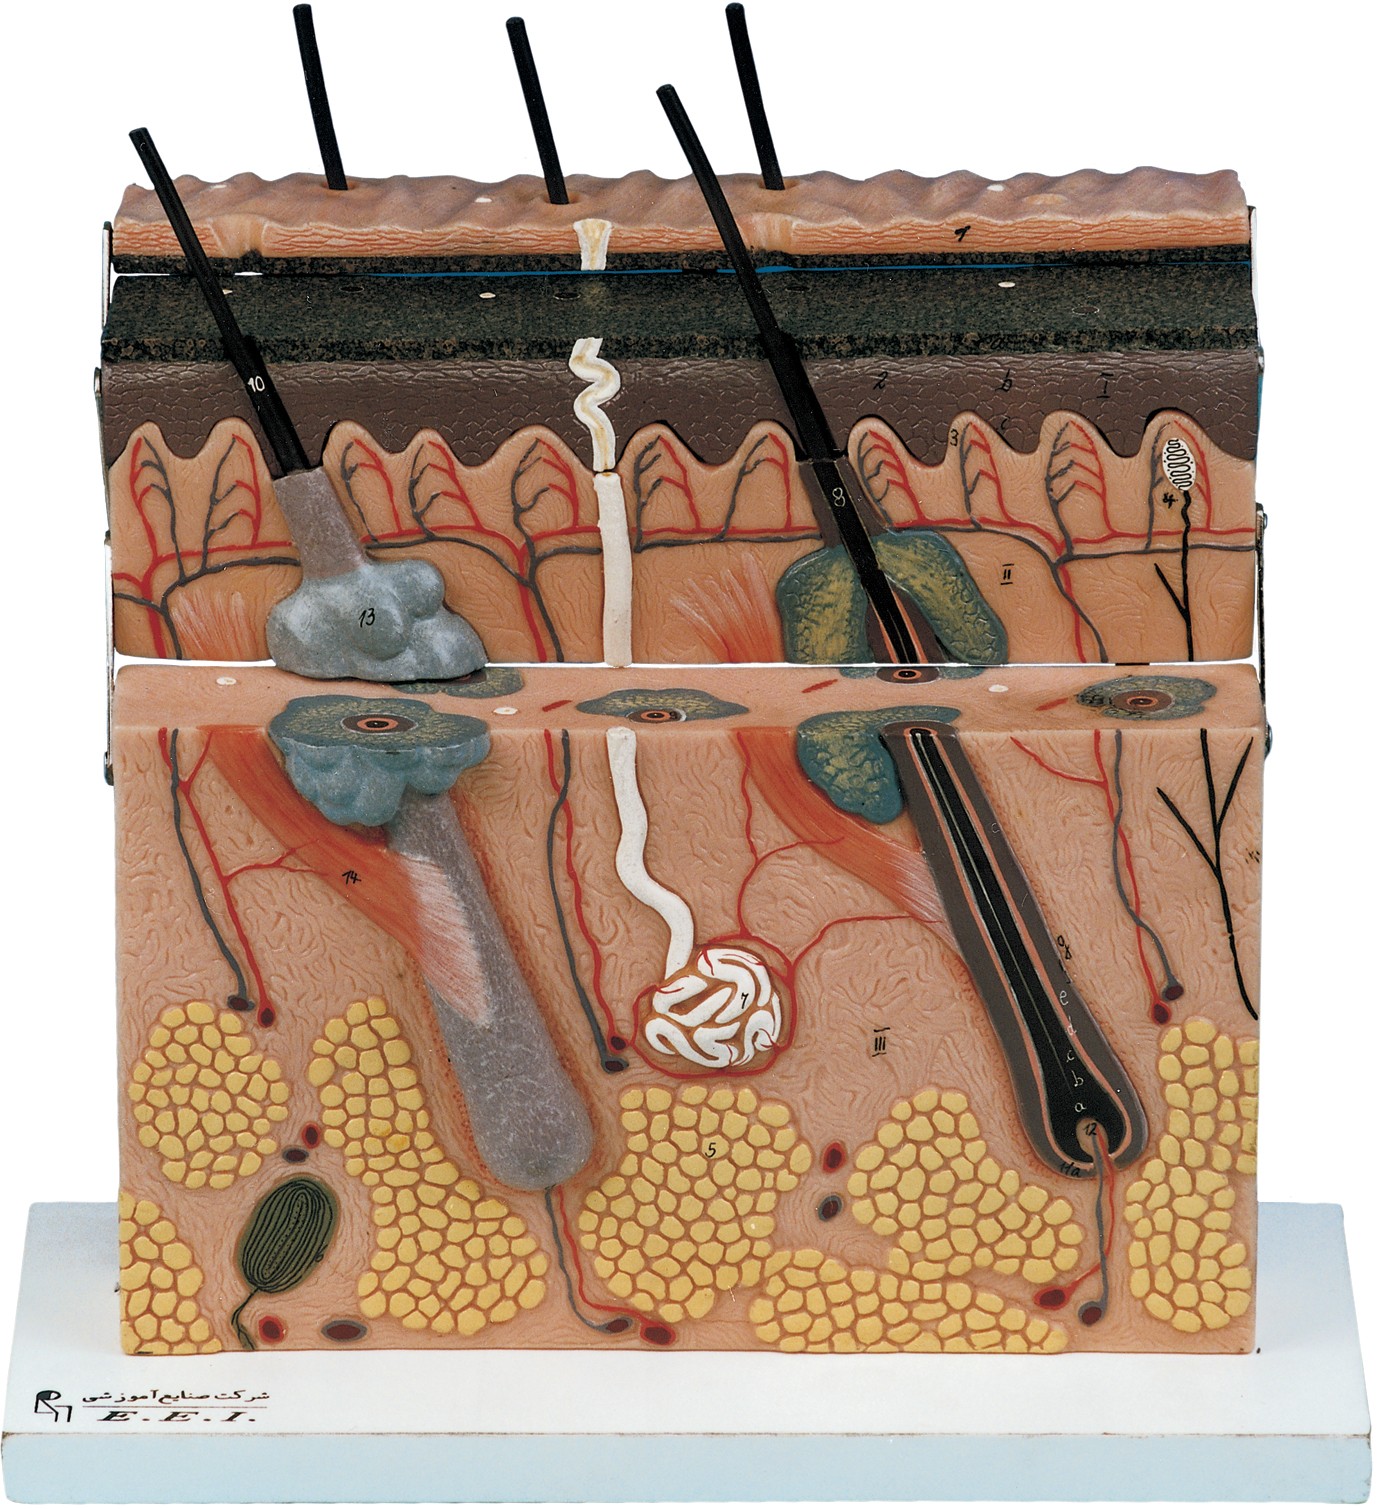

مولاژ کلمه ای فرانسوی به معنای قالب است. آناتومی بدن انسان با تجهیزاتی مانند مولاژهای پزشکی یا کالبدشناسی که نمونه هایی تخصصی و شبیه به اندام های بدن انسان هستند، به دانش آموزان و دانشجویان آموزش داده می شود. استفاده از مولاژ در روند یادگیری و آموزش تاثیر به سزایی داشته و تمامی اندام ها را با تمامی جزئیات و با کیفیت بالا می توان مشاهده و بررسی کرد. مولاژها عموما از جنس PVC نشکن، لاستیک یا فوم ساخته شده و دارای رنگ طبیعی و قابل شست و شو هستند. برخی از انواع مولاژها مناسب برای آموزش مراقبت های پزشکی و پرستاری است و امکان تمرین بانداژ، تزریق، CPR، جراحی و... وجود دارد. مولاژها معمولا هر کدام عضوی از بدن را نمایش می دهند و قابلیت تفکیک و مشاهده همه بخش های آن وجود دارد.

مولاژها معمولا با توجه به نوع اعضا و یا دستگاه های بدن در اندازه طبیعی، کوچکتر و یا چندین برابر بزرگتر ساخته می شوند تا امکان مشاهده دقیق اجزای آن ها فراهم شود. برخی مولاژها از چندین قطعه ساخته شده اند که قابلیت تفکیک دارند. علاوه بر نمایش ساختار و نحوه عملکرد اعضای بدن، ماهیچه ها و عضلات بدن را نیز می توان به کمک مولاژها مشاهده کرد.

مولاژها ابزاری تخصصی برای آموزش دانشجویان پزشکی، دندان پزشکی، پرستاری و مامایی است. همچنین در مدارس و سایر مراکز آموزشی میتوان از انواع مولاژها برای بهبود یادگیری و آموزش بهره برد. در کلینیک های زنان و زایمان، دندان پزشکی، سالن های تشریح، بیمارستان ها و آزمایشگاه ها نیز مولاژهای مراحل حاملگی، انواع دندان و بیماری های آن کاربرد دارند.